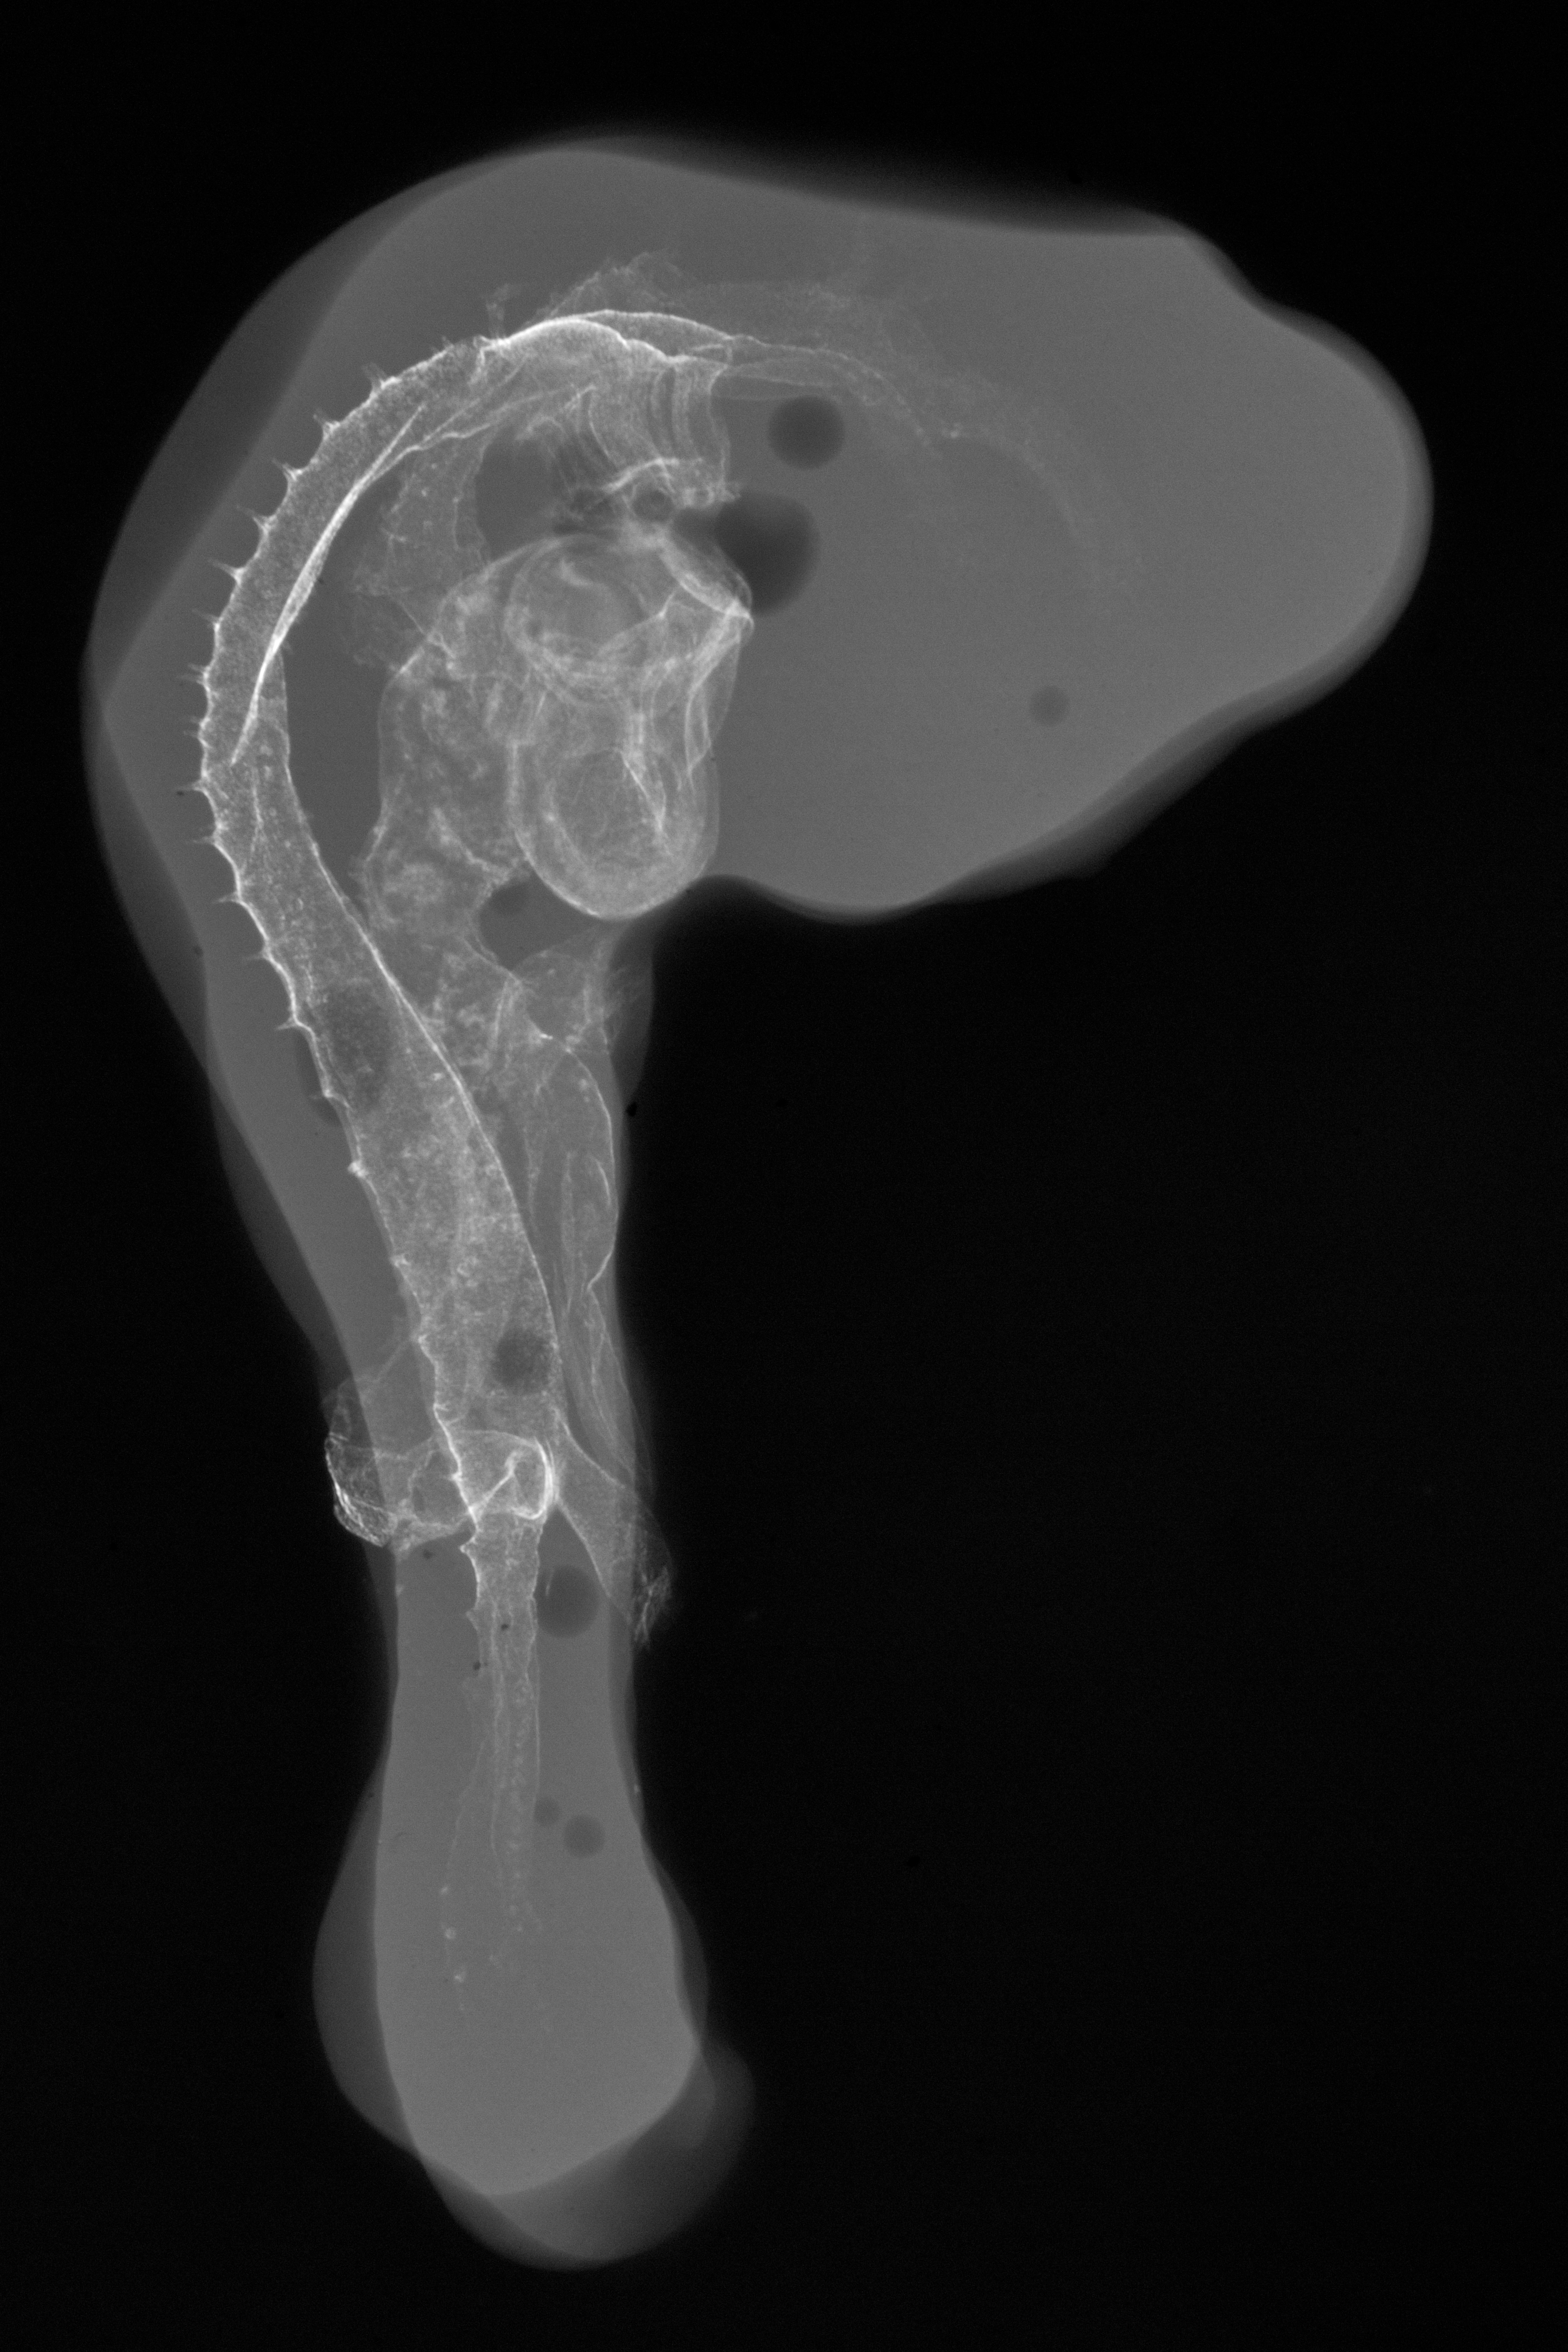

Chick Embryo Microangiography

Hamburger-Hamilton (HH) Stage 20 (approx. 3 - 3.5 days)

X-Ray Micrographs